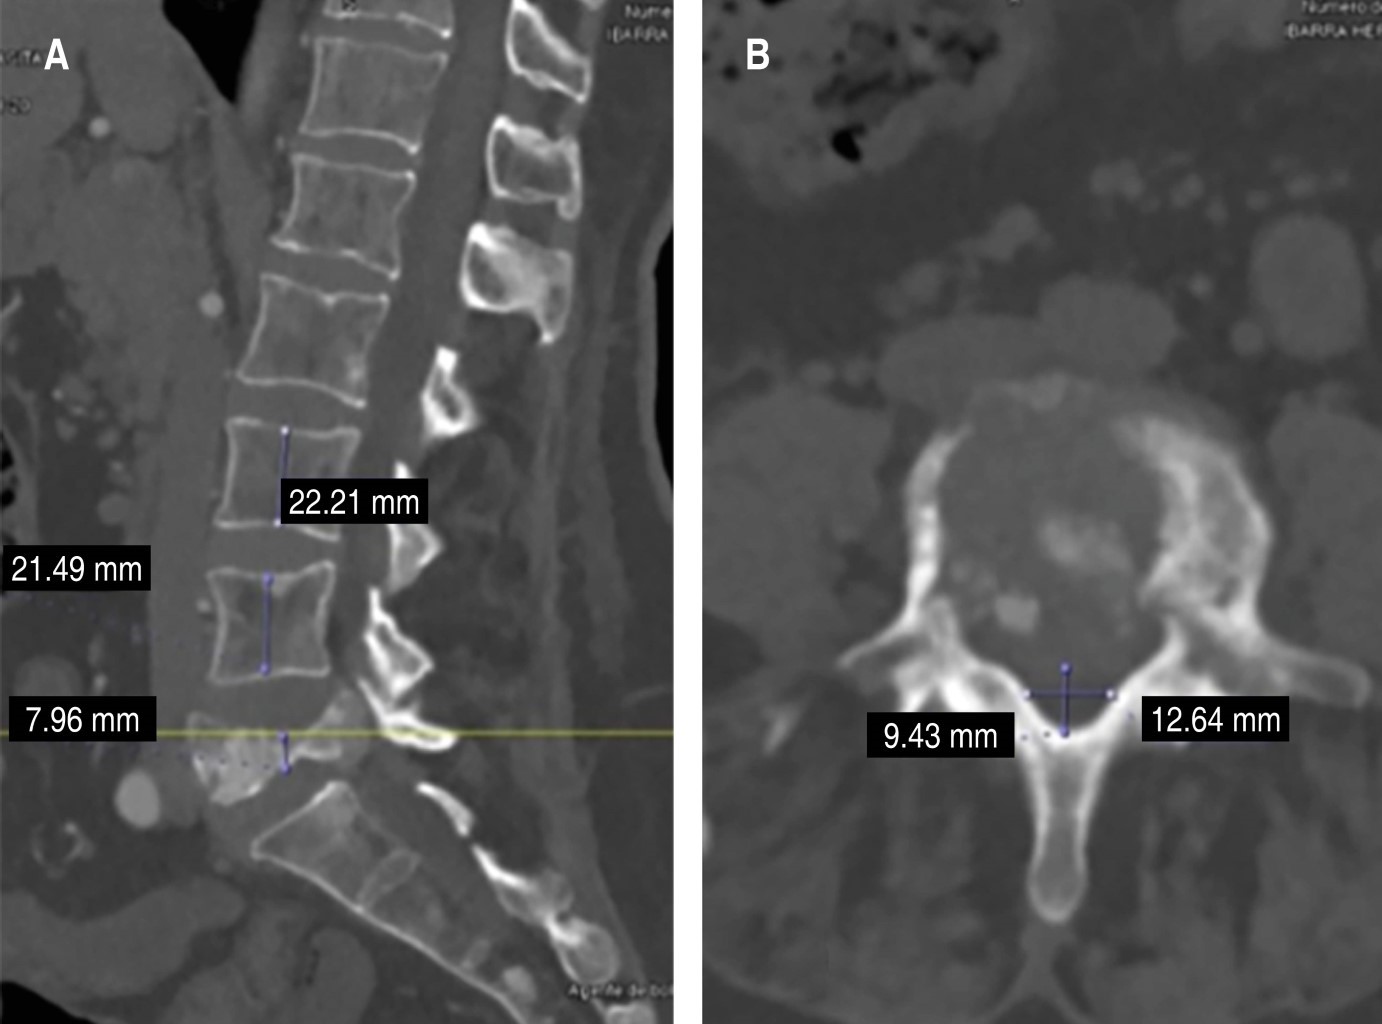

Recibimos paciente en consultorio con facies claras de dolor, sin tolerar la deambulación ni la sedestación, fuerza muscular para ambos miembros pélvicos 3/5 en todos los grupos musculares interferida por la generación de dolor a la movilización. Refiere adecuado control de esfínteres. Se solicitan radiografías en doble proyección como método de diagnóstico inicial, en donde se observa lesión en cuerpo vertebral L5, con aparente destrucción del mismo, por lo que se decide complementar el protocolo de estudio mediante serie ósea metastásica, tomografía axial computarizada (TAC) abdominopélvica y de columna-tórax y resonancia magnética simple de columna. A la revisión de la TAC de columna se observa la presencia de lesión lítica de quinto cuerpo vertebral lumbar, con afectación del muro posterior (Figura 1). En la resonancia magnética se describe la existencia de lesiones hiperintensas en L5 ocasionando compresión e invasión hacia canal medular de aproximadamente 70%. Considerando el aumento de la sintomatología más el grado de compresión, se considera realizar tratamiento quirúrgico consistente en descompresión mediante lumbotomía de L5 por abordaje anterior más colocación de malla con injerto autólogo e instrumentación transpedicular L3-S1 con aumento a iliacos y envío de la muestra obtenida por corpectomía a patología y cultivo (Figura 2). Se obtienen resultados de patología a las dos semanas posteriores, en donde se reporta muestra macroscópica compatible con carcinoma folicular de tiroides, motivo por el cual se solicita valoración por servicio de oncología y oncocirugía, en donde se realiza como complemento de estudio ultrasonido Doppler de tiroides objetivándose presencia de nódulos tiroideos, por lo que se inicia protocolo quirúrgico para realización de tiroidectomía total. Después de ambos procedimientos quirúrgicos, la paciente muestra adecuada evolución clínica sin datos de proceso infeccioso agregado iniciando deambulación progresiva y con seguimiento por medio de la consulta externa por servicios correspondientes (Figura 3).